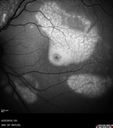

Multifocal Vitelliform Macular Dystrophy515 views58 year old female with mild vision loss - 20/20 OU - extensive testing has shown no cancer. Case of Karina Findlay, MD